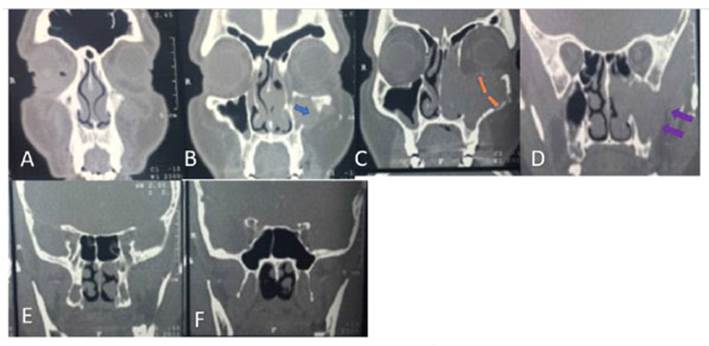

Acude con tomografía computada (TC) de nariz y senos paranasales donde se observa tumor proveniente aparentemente de seno maxilar izquierdo el cual amplio meato medio con extensión hacia fosa nasal el cual invade piso de orbita desplazando recto inferior también invade fosa subtemporal ipsilateral. Exploración física: Otoscopia bilateral cae permeables, membranas timpánicas integras. Rinoscopia anterior y nasofibroscopia flexible: septum funcional: presencia de lesión en fosa nasal derecha la cual se extiende hacia nivel coanal de consistencia lisa, aparentemente vascular, violáceo (Figura 1).

Figura 1 Tomografía contrastada ventana para tejidos blandos corte coronal, donde se aprecia una lesión que se ubica en el seno maxilar izquierdo (flecha azul Imagen B), de aspecto expansivo, con lisis ósea de sus paredes con extensión a borde inferior de "anillo" óseo orbital, (flechas naranjas Imagen C) con infiltración de la grasa, se extiende a toda la cavidad nasal ipsilateral y espacio masticador (flechas moradas Imagen D).

En la TC simple de nariz y senos paranasales en fase arterial encontrada lesión isodensa que no capta de forma importante el material de contraste (TC coronal), se procede de realizar biopsia en sala quirúrgica por abordaje de degloving facial trans quirúrgica (Figura 1).